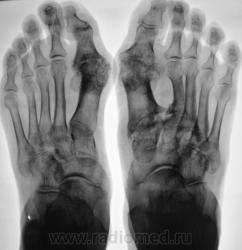

Пациентка направлена на рентгенографию стоп в прямой проекции с диагнохом - "Поперечное плоскостопие"

Пациентка направлена на рентгенографию стоп в прямой проекции с диагнохом - "Поперечное плоскостопие".

Произведена рентгенография обеих стоп в прямой проекции.

Думаю, что это дисхондроплазия - болезнь Олье.

Сильно сомневаюсь в болезни Олье - затронуты только суставные концы, диафизы интактны. Считаю - остеоартропатия, вероятнее всего - подагра

мне тоже почему то о подагре сразу подумалось)))))а что в анализах?

Классика подагры - наличие тофусов в параартикулярных мягких тканях... Механизм поражения скелета при подагре - атрофия от давления тофусами. А здесь - их совершенно не видно, мягкие ткани просто отодвинуты, но обьем то их - нормальный...

Согласен с артропатией, но подагра - сомнительно....

Поскольку артропатий великое множество....почему бы и не псориатическая...к примеру. Как там с анамнезом?

Пациентка весьма преклонного возраста - за 70 лет.